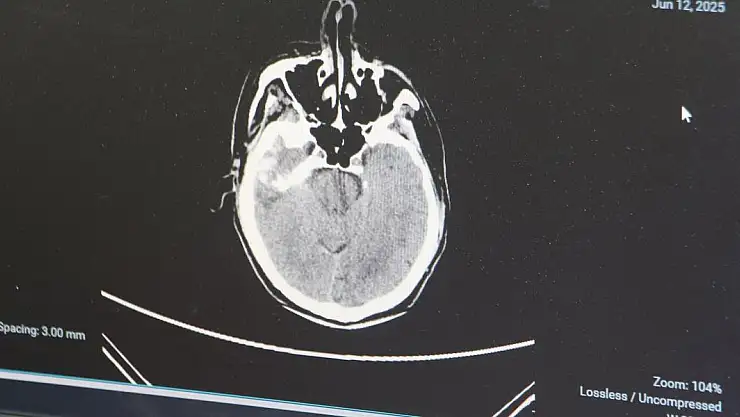

Genellikle 50 yaştan sonra görülen beyin kanaması, son yıllarda gençlerde daha sık görülmeye başlandı. Sebeplerine dikkati çeken Adana Şehir Hastanesi Beyin ve Sinir Cerrahisi Bölümü'nden Doç. Dr. Ali İhsan Ökten, bunların daha çok "arteriyovenöz malformasyon" ve "anevrizma" kaynaklı yaşandığını söyledi. Anevrizma, yani kan damarlarının duvarında oluşan baloncuk şeklindeki patolojik genişlemeler kaynaklı yaşanan beyin kanamalarının 100 binde 10 ile 15 kişi arasında görüldüğünü dile getiren Doç. Dr. Ali İhsan Ökten, "Gençlerde görülme oranı giderek artıyor" dedi